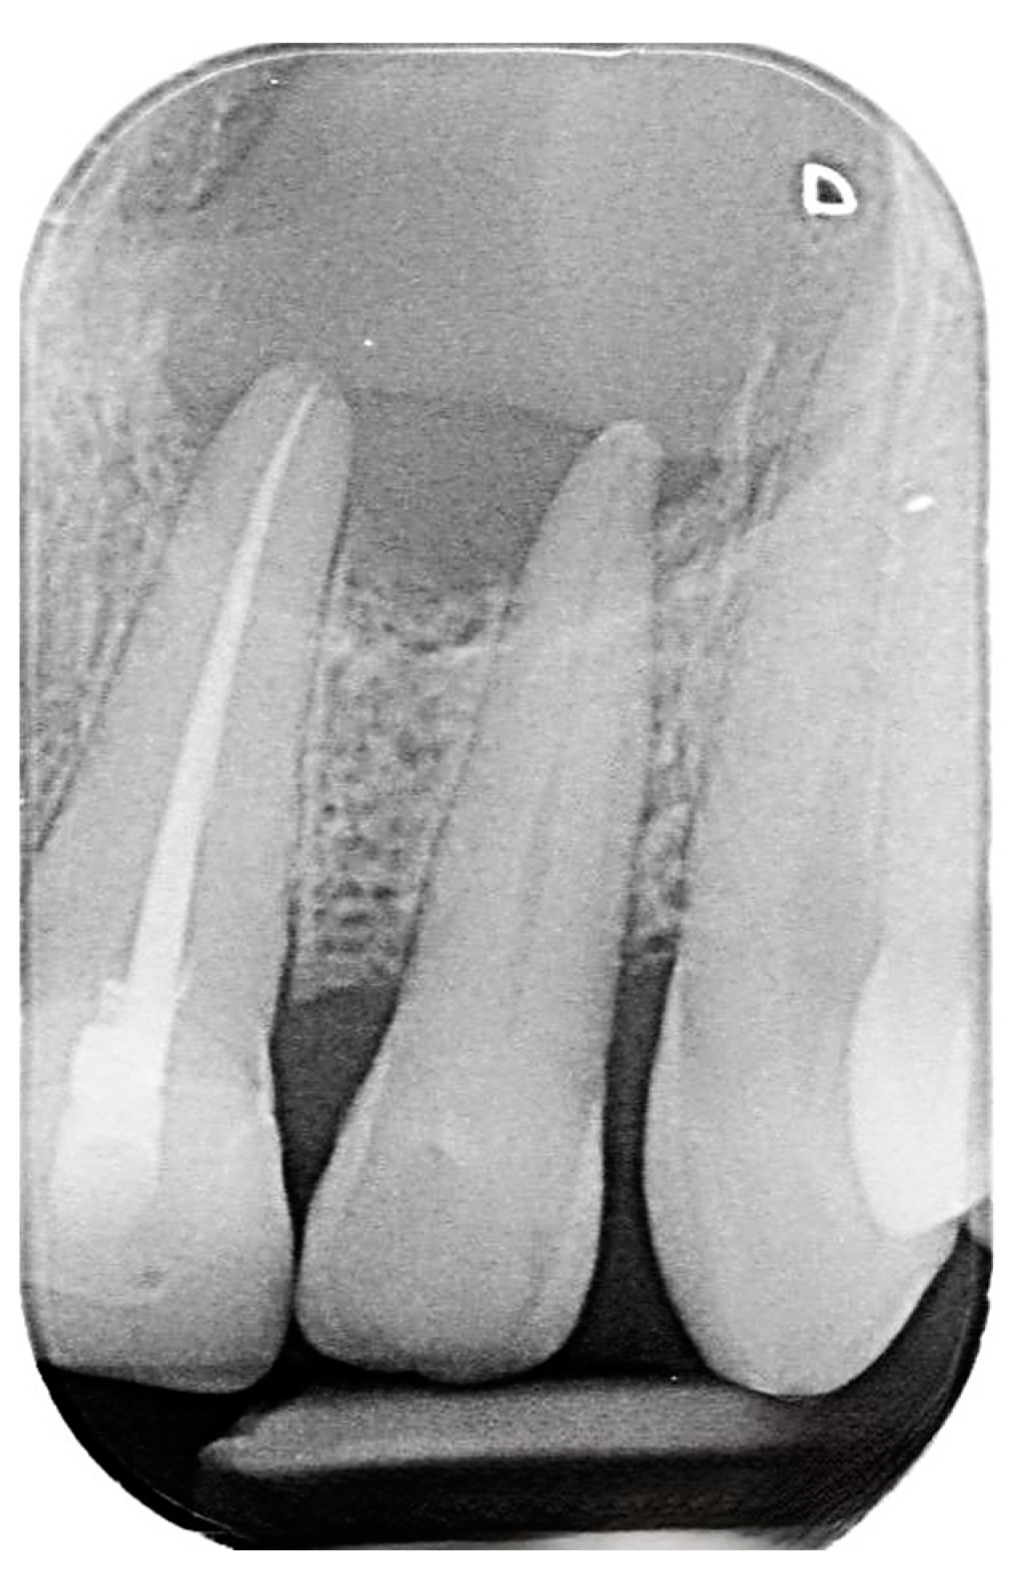

2. Case Presentation

2.2. Delivery of Treatment

2.4. Healing of the Defect and Follow Up